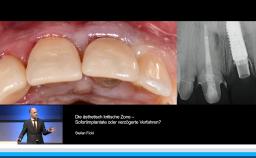

Implantatverlust mit Defektsituation: Erneute Implantation oder Alternativtherapie?

Basierend auf diversen Studien und eigener klinischer Erfahrung stellt Dieter Weingart seine Erkenntnisse und Schlussfolgerungen zum Thema Implantatverlust mit Defektbildung vor. Er illustriert das Thema mit eigenen klinischen Fällen inklusive Langzeit-follow-ups.